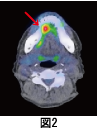

舌の右下面に痛みを感じて、総合病院の口腔外科受診された60歳代の男性です。舌下面に径15×15㎜の潰瘍が出来ていて、生検を行ったところ、がんが見つかった方です。転移も疑われたのでPET検査を行いました。その結果が図1の全身像と、図2の舌がんの部分です。この方は幸いにも舌がんの部分のみに集積を認め、転移はありませんでした。